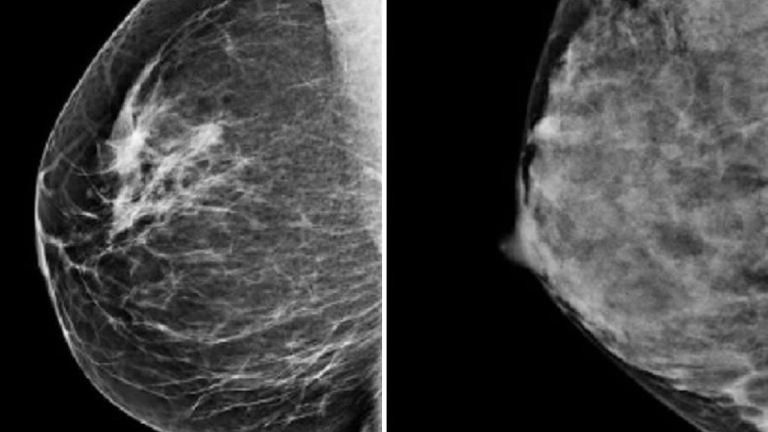

This is because denser breasts look whiter on mammograms, which makes it harder to spot small early-stage cancers which also appear white.